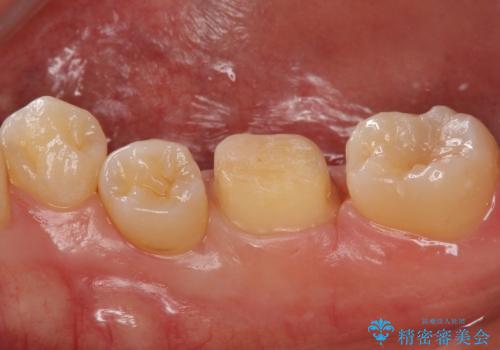

奥歯の詰め物の変色 セラミッククラウンでのやり替え

- 左下に詰めた樹脂の変色を主訴に来院されました。

同じ樹脂の材料で詰め直しをしたところでまた変色してしまうリスクが高いため、セラミックでの治療となりました。